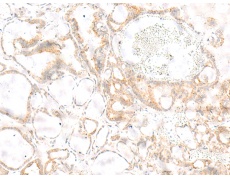

IHC positive control: |

Human thyroid cancer |

IHC Recommend dilution: |

10-50 |